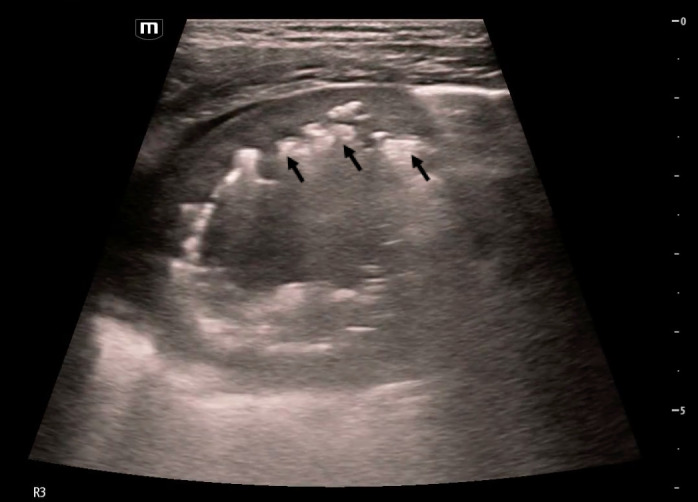

Application of ultrasound to evaluate pediatric respiratory disease in the emergency department setting is rapidly growing, particularly as we often weigh the risks of exposure to radiation with other readily available imaging modalities in the acute care setting. In this case report, we describe how point of care ultrasound (POCUS) was utilized by emergency providers to characterize a lung abscess diagnosed in a pediatric patient. We also compare the ultrasound findings to other imaging studies.

Abstract Image